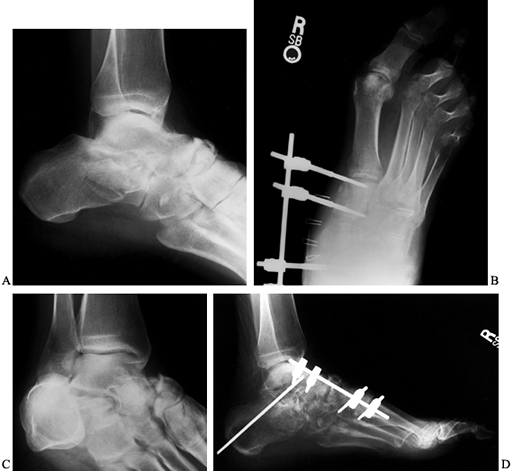

as medially from the talar neck to the first metatarsal (Fig. 111.1C, Fig. 111.1D) (11,15)

Figure 111.1. Lateral (A) and oblique (B) radiographs of a comminuted subtalar and talonavicular fracture dislocation. AP (C) and lateral (D) radiographs demonstrating external fixation to stabilize the medial column.